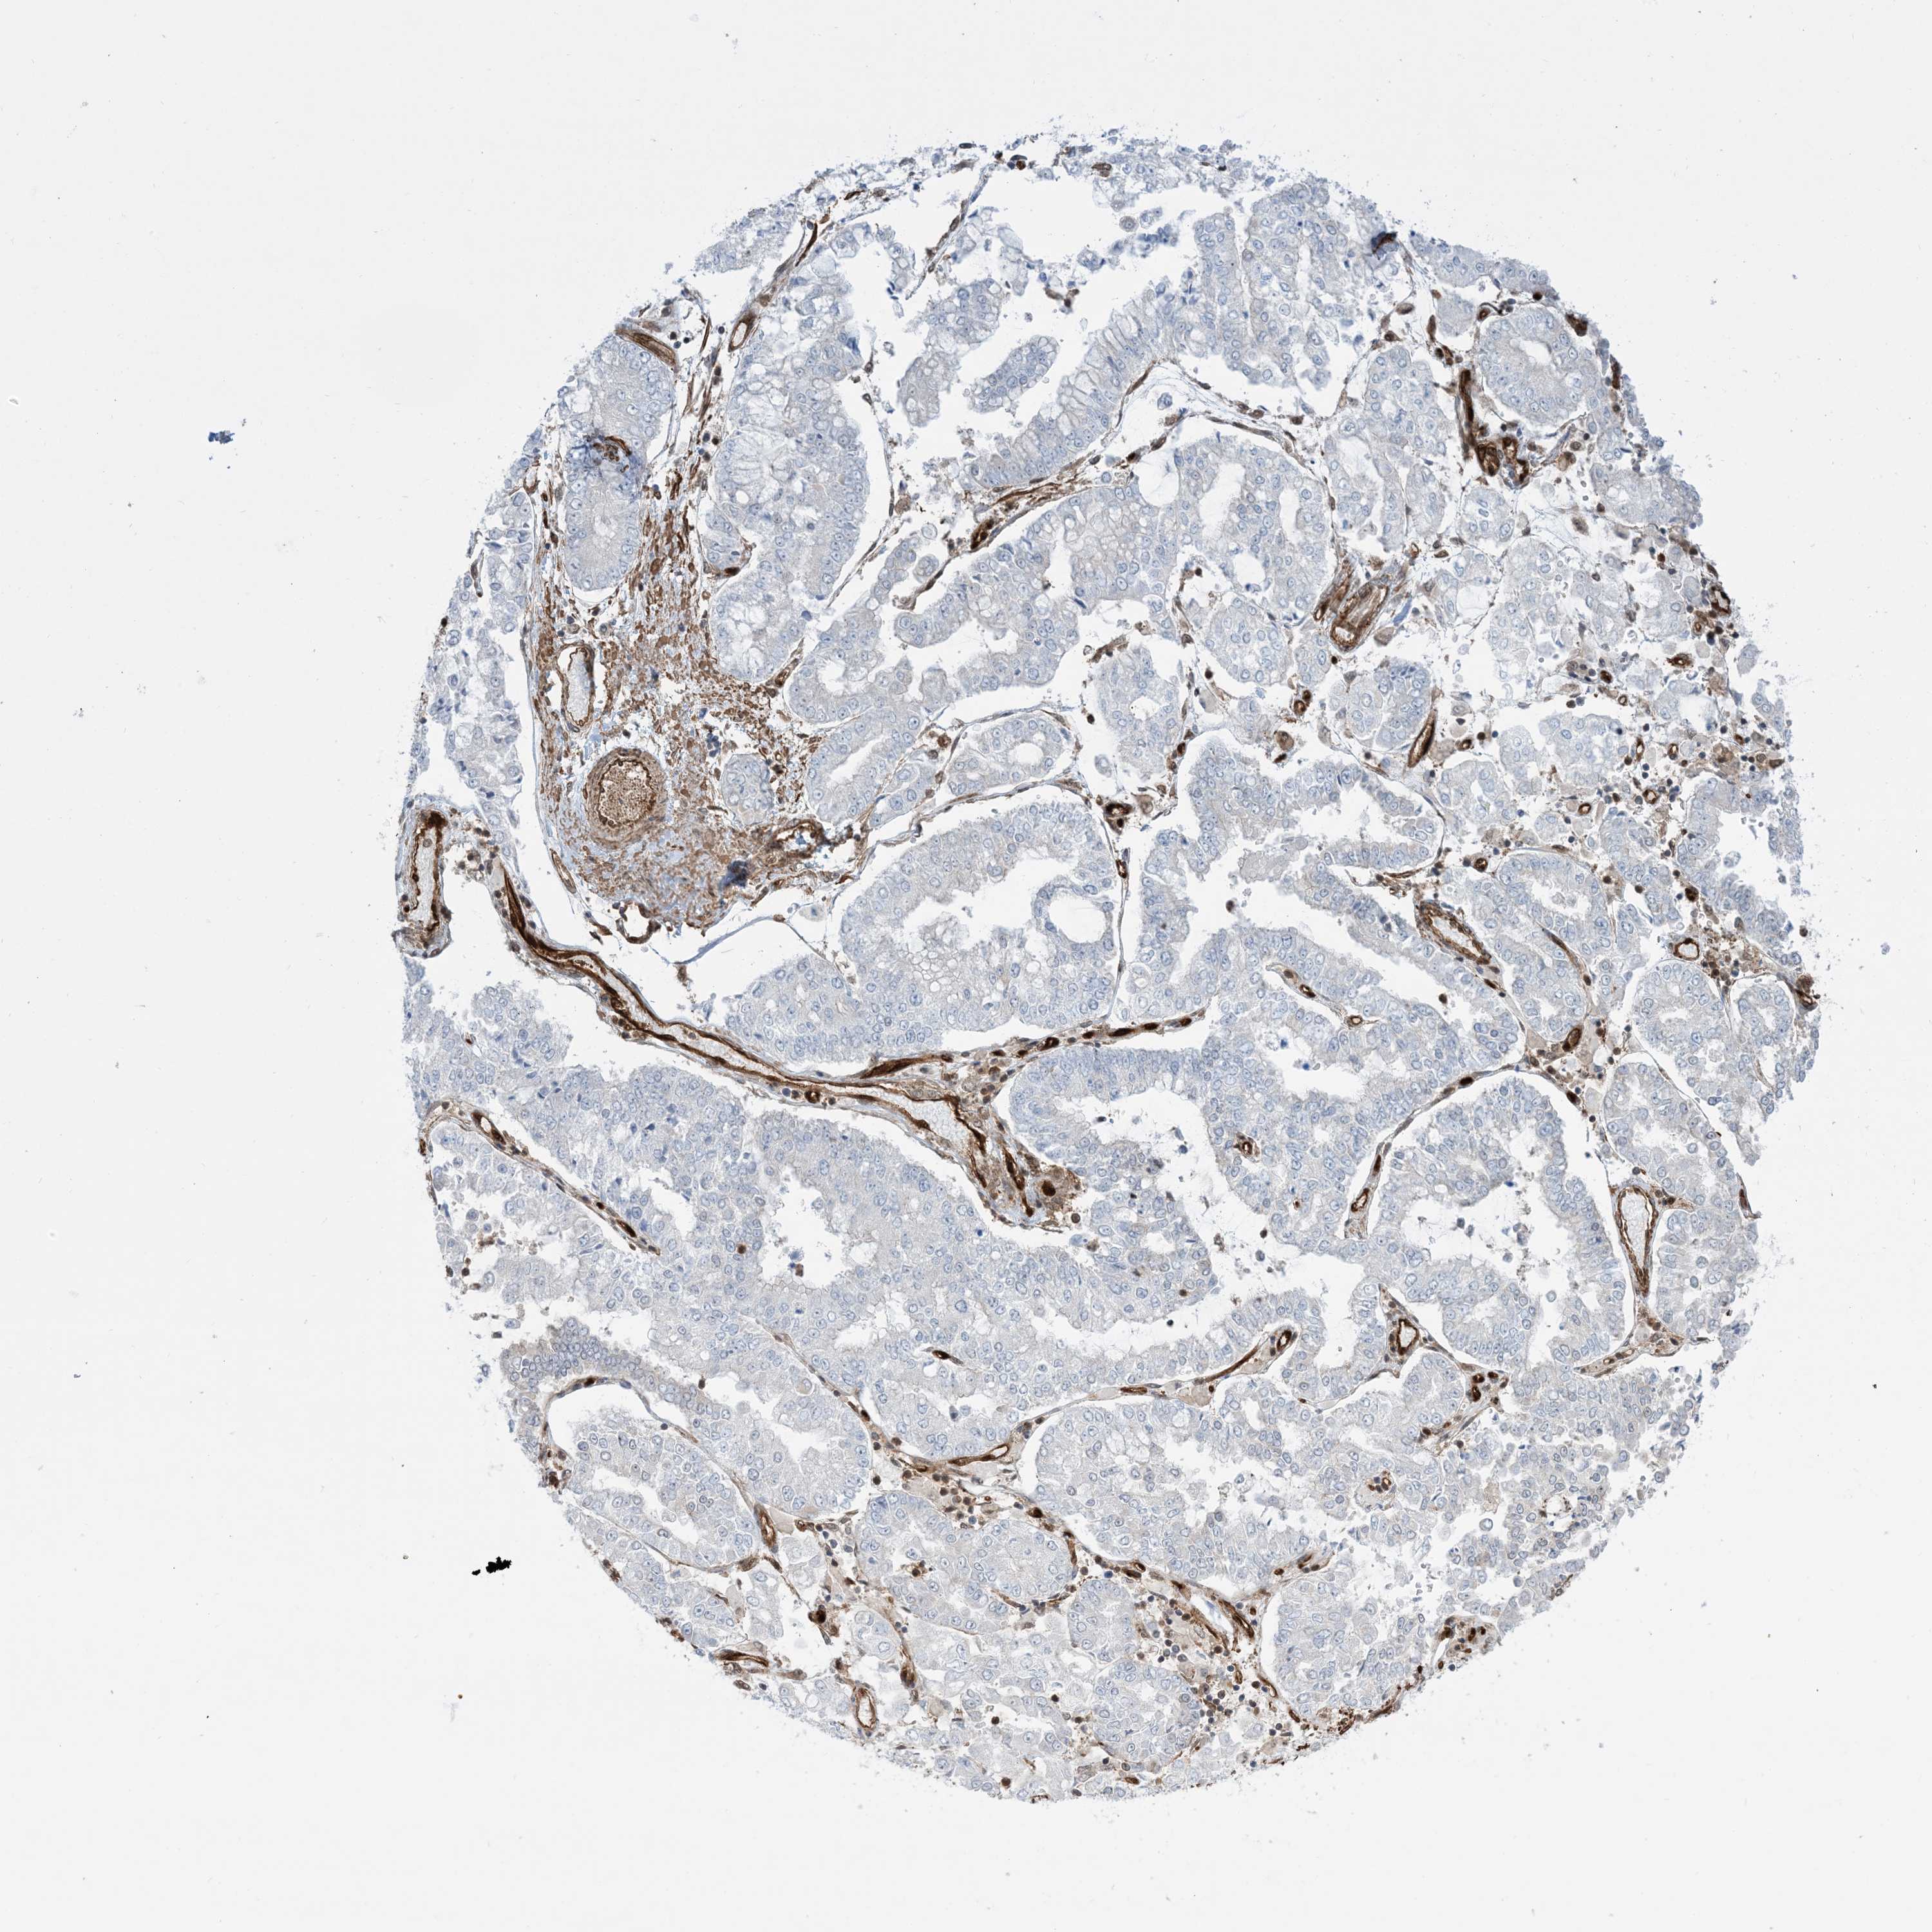

STOMACH CANCER - Protein expressioni

A mouse-over function shows sample information and annotation data. Click on an image to view it in a full screen mode. Samples can be filtered based on level of antibody staining by selecting one or several of the following categories: high, medium, low and not detected. The assay and annotation is described here.

Note that samples used for immunohistochemistry by the Human Protein Atlas do not correspond to samples in the TCGA dataset.

Antibody stainingi

Antibody staining in the annotated cell types in the current human tissue is reported as not detected, low, medium, or high, based on conventional immunohistochemistry profiling in selected tissues. This score is based on the combination of the staining intensity and fraction of stained cells.

Each image is clickable and will lead to virtual microscopy that enables deeper exploration of all samples and also displays staining intensity scores, fraction scores and subcellular localization as well as patient and tissue information for each sample.

Antibody HPA030989

Antibody HPA030990

Staining

High

Medium

Low

Not detected

Intensity

Strong

Moderate

Weak

Negative

Quantity

>75%

75%-25%

<25%

None

Location

Nuclear

Cytoplasmic/membranous

Cytoplasmic/membranous,nuclear

Adenocarcinoma, NOS